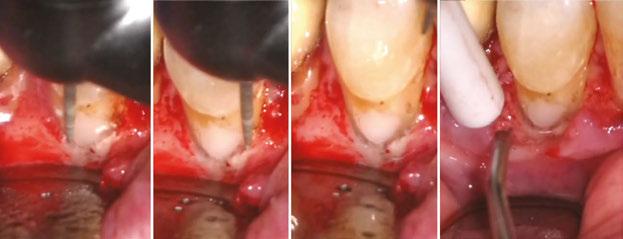

On the day of the surgery, before commencing the procedure under strict asepsis, the patient was asked to rinse with 0.12% chlorhexidine gluconate mouthwash (Peridex™; 3M™). Local anesthesia with a vasoconstrictor was infiltrated buccally and palatally into the posterior and anterior maxilla on both the sides using S-blades (straight) (Zabby, India). The incision was made

on the crest of the ridge in the region of teeth Nos. 15-25. While creating the incision, bleeding was noticed in the region of tooth No. 15 which intensified during the flap reflection (Figure 2). Bleeding was pulsatile, indicating an arterial bleed. Initially attempts to control bleeding included a pressure pack and ice pack, and the bleeder was isolated, and the vessel ligated (Figure 3). The bleeding could be controlled, and the procedure was completed by placing four Bioner implants (Bioner, Spain), size 4/10 mm. Sutures were placed, and patient was kept on basic medication for pain and infection control. Immediately after the surgery, the patient was advised to get a CBCT. As shown in Figure 4, a coronal view and Figure 4B (yellow arrows), the position of the artery can be seen.

Figure 1: Pre-op panoramic radiograph Figure 2 (left): Alveolar antral artery (AAA). Figure 3 (center): The artery has been ligated with suture. Figures 4A and 4B (right): CBCT post-implant placement and position of the artery coronally (top). 4B. Showing the position of alveolar antral artery (AAA) in relation to implant placement as indicated by the yellow arrows (bottom)